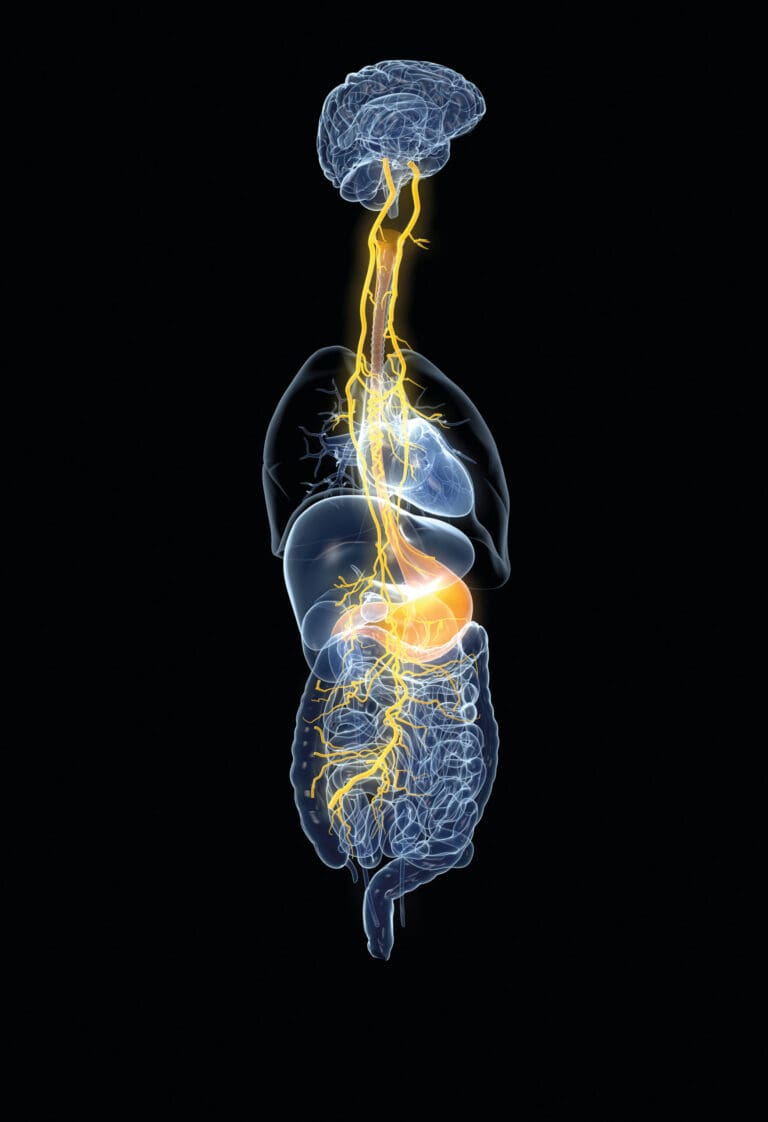

As part of the bidirectional gut-brain axis, afferent vagal nerves send signals from the bottom-up. There is reason to believe that these vagus nerve pathways might serve as a type of “serotonin superhighway” between the gut and the brain.

If a picture is worth a thousand words, this early anatomical drawing of the vagus nerve (below) speaks volumes. As you scroll down this narrow-and-long image, try visualizing how your vagus nerve facilitates communication along your gut-brain axis as part of a bidirectional feedback loop.

The vagus nerve is also called the “wandering nerve” because it’s the longest nerve in the human body and has countless branches that wind their way from the brainstem all the way down to the lowest part of the intestines, touching most major organs along the way. The vagus nerve modulates the parasympathetic nervous system, which counterbalances the fight-or-flight stress response by eliciting the so-called “relaxation response.”